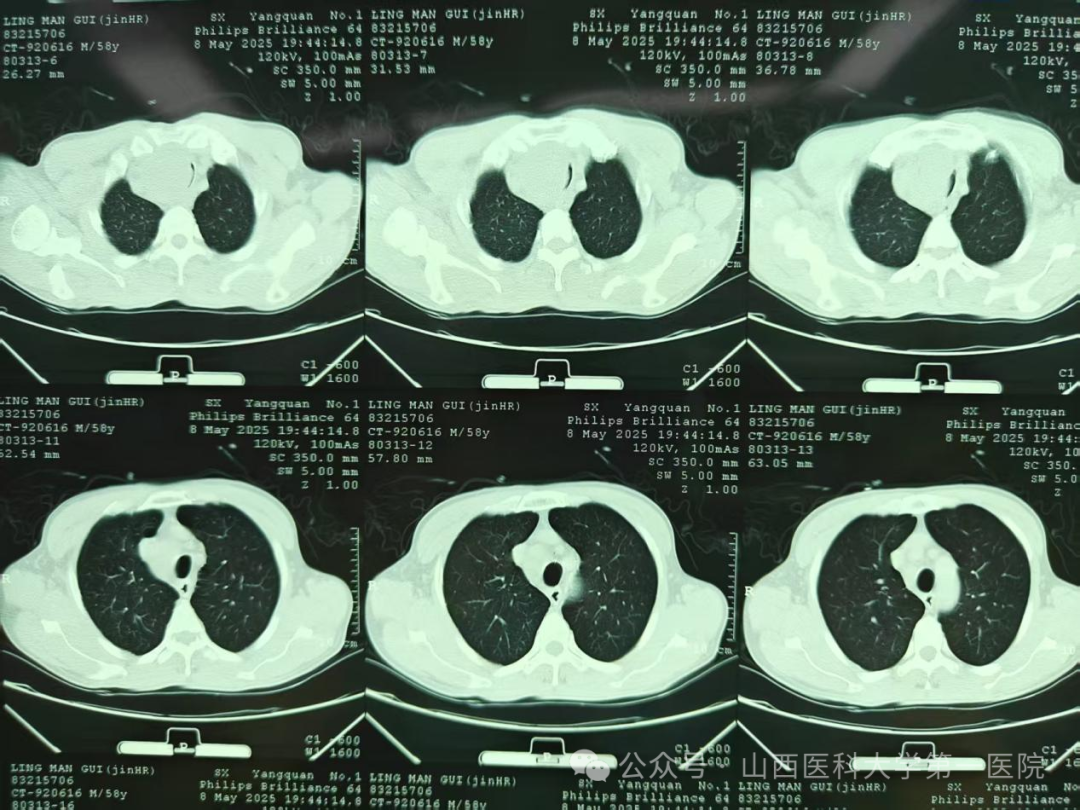

支气管镜下可见气管上端重度狭窄

当日晚上9点,呼吸介入团队成员任寿安、郭志宏、尹建升、李艳青、王琛在手术室为患者在局部麻醉下行支气管镜检查,发现气管上段呈新月形外压性狭窄,管腔狭窄约95%,任寿安、郭志宏主任医师迅速置入气道支架,完全覆盖狭窄部位,麻醉科郭志佳副教授全程保驾护航。整个过程有惊无险,患者呼吸困难得到明显改善,平卧返回重症医学科密切观察。